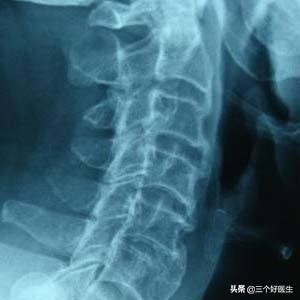

第四个阶段已经进入到了老化期,某些关节完全绞索,甚至锁死,椎间盘缩水更加严重,脊椎关节的功能基本上丧失,骨质增生非常明显甚至严重到上下椎体形成骨桥。该阶段的临床表现可能会出现持续性的疼痛,跛行,严重的驼背和脊柱侧弯,情况严重的可能会影响到相关的脏腑,并影响正常的器官功能。椎管可能狭窄,神经血管受压更加严重。该阶段对应的年纪大约在65岁以上。

C4/5骨桥形成,C2/3唇样增生

第四阶段的治疗已经显的很苍白了,矫正只能缓解部分症状,减轻部分痛苦,正骨治疗已经不能作为主要的治疗方法了,甚至有的时候还属于正骨的禁忌症。如果症状严重通过手法治疗无效则考虑手术治疗。